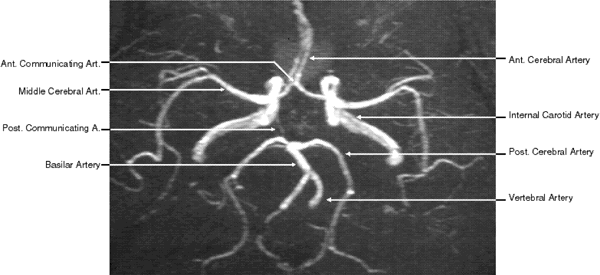

With 2D TOF, multiple thin imaging slices are acquired with a flow-compensated gradient-echo sequence. Slice thickness is limited to 1.5 mm. These images can then be combined by using a technique of reconstruction such as maximum intensity projection (MIP) to obtain a 3D image of the vessels analogous to conventional angiography (Fig. 11). The 2D TOF MRA technique is robust and relatively fast; it may be adequate for screening, but it is less accurate for gauging the degree of stenoses.

Fig. 11. Two-dimensional time-of-flight magnetic resonance angiography of the circle of Willis (superior view).